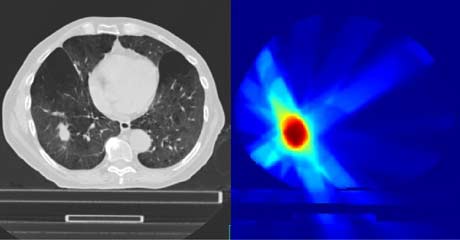

El cálculo de la dosis en los tratamientos de radioterapia externa es un desafío por la alta conformación de los haces de radiación en la tecnología actual (IMRT y VMAT). Estas técnicas adaptan los haces a la forma del tumor, de manera que la dosis recibida por los tejidos sanos es pequeña, pero el coste asociado es que cualquier error de posicionamiento o el movimiento del propio tumor (por ejemplo, por respiración) puede afectar a la dosis depositada.

Esta línea tiene por objeto utilizar herramientas de adquisicón de imagen (Cone Beam CT) y de procesado de imagen médica (registro deformable) para determinar la dosis real recibida por un paciente en cada sesión de tratamiento y así poder adaptar las sesiones restantes para alcanzar la dosis prescrita.

La dosis recibida por el tejido sano es de especial importancia cuando los pacientes son pediátricos o cuando se van acumulando tratamientos radioterápicos. Para este tipo de tratamientos está especialmente indicada la radioterapia con protones, disponible en la sede de Madrid de la Clínica Universidad de Navarra. En esta línea buscamos resolver los problemas asociados al Pencil-Beam Scanning y el movimiento interno del tumor.

En esta línea buscamos optimizar el procedimiento y la dosis en el caso de tumores pulmonares y oculares empleando desarrollos propios tanto de equipamiento como de herramientas computacionales